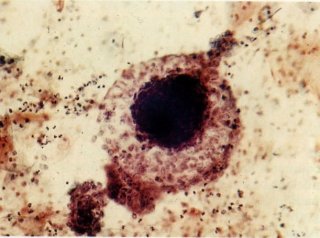

38. Células endometriais. Este campo mostra um grupo de células do estroma e poucas células isoladas parecendo-se com histiócitos (topo), as quais são provavelmente de origem glandular (flecha). (X 160)

É normal e achar células endometriais do esfregaço Cérvico vaginal dois a três dias antes, durante e por poucos dias após a menstruação. Em algumas mulheres ocasionalmente a células endometriais são vistas no meio do ciclo na época da ovulação; isto pode ser também associado com a “mittelschmerz” (dor na ovulação). Mulheres usando um dispositivo intra-uterino contraceptivo (DIU) e geralmente desprendem células endometriais através do ciclo, mas com esta exceção as células endometriais achadas fora dos tempos especificados acima deveriam ter investigação adicional. Em particular, células endometriais achadas em esfregaços na pós-menopausa freqüentemente indicam doença mesmo quando as células parecem normais.